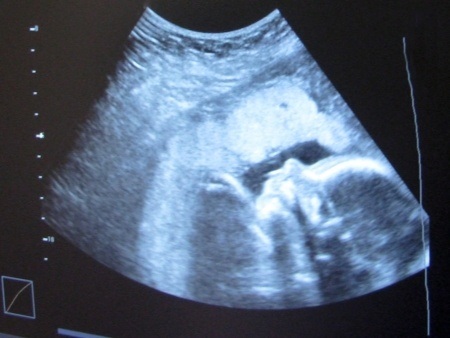

הרשלנות התבטאה בשחרורה של האם מהמיון למרות תלונותיה על ירידה בתנועות העוברית, ומבלי שבוצעה בה בדיקת אולטראסאונד, וזאת אף שבטופס השחרור נכתב כי הבדיקה בוצעה.

בשבוע ה-39 היא הגיעה למיון איכילוב והתלוננה על ירידה בתנועות העוברית. לאחר בדיקת אחות, רופא מתמחה החליט, באישור הרופאה האחראית, לשחרר אותה עם הנחיות למעקב. פחות מ-48 שעות לאחר מכן, התובעת חזרה למיון ובבדיקות התגלה שלעוברית אין דופק.

ב-2014 הגישו התובעים את תביעתם באמצעות עוה"ד אבי שמואלי. התובעת סיפרה שהיא שוחררה מהביקור הראשון במיון ללא בדיקת אולטרסאונד – אף שבמכתב השחרור נכתב שכן בוצעה.

בהקשר זה התובעים הציגו מכתב מבית החולים, שניתן במענה לפניית בא כוחם לקבל את המידע על אודות ביצוע הבדיקה, ובו נכתב במפורש שאין בדיקה כזו.

התובעים טענו בין היתר כי מותה של העוברית היה יכול להימנע אילו היו עושים את הבדיקה או מאשפזים את התובעת.

מנגד, המדינה והעירייה – אותן ייצג משרד עו"ד סהר סטביצקי ושות' – טענו בין היתר כי לתובעת נערכה בדיקת אולטרסאונד, והסיבה שהדבר לא הופיע במכתב התשובה מטעם בית החולים היא כי המכשיר בו בוצעה אינו מחובר למערכת הממוחשבת ולכן הנתונים לא אותרו.

במחלוקת לגבי האולטרסאונד, השופט חדיד העדיף את גרסת התובעת. הוא קבע כי מכתב התשובה נחשב ל"הודאה" ואף לא האמין שעורכת הדין המנוסה שחתומה עליו לא בחנה את פרטי המקרה בפרוטרוט.

לעומת זאת, הרישום בגיליון השחרור לא עמד בנהלי משרד הבריאות או בחובת התיעוד המוטלת על בית החולים. כך למשל, לא נרשמה שעת הבדיקה או זהות הבודק וגם לא משקל העוברית.

לפיכך נקבע כי הצוות הרפואי התרשל בכך שנמנע מביצוע הבדיקה החיונית.